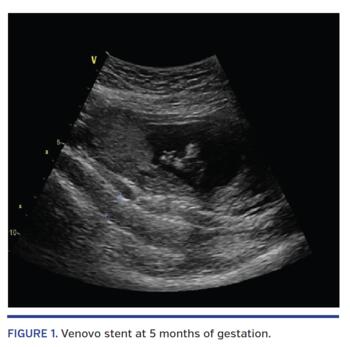

The patient is a young female who presented with debilitating left leg pain. Computed tomography angiography of the abdomen and pelvis revealed a severe compression of the left common iliac vein by her right common iliac artery. The patient underwent venography and intravascular ultrasound to her left iliac veins. The left common iliac vein was severely compressed by the right common iliac artery with luminal area stenosis ranging from 80% to 90% when compared with the ipsilateral distal left common iliac vein reference. Stenting was carried out using an 18 x 60 mm Venovo venous stent. Repeat duplex ultrasound at 5 months into her pregnancy (Figure 1) showed no evidence of iliac vein compression and the stent was widely patent. At 33.5 weeks into her pregnancy, another duplex ultrasound was performed (Figure 2) and showed no evidence of stent compression by the gravid uterus and good flow. Computed tomography scan of the pelvis with venous filling was performed 2 years after her pregnancy. The stent was widely patent with no restenosis, thrombosis, compression, or deformation and with optimal positioning (Figure 2).